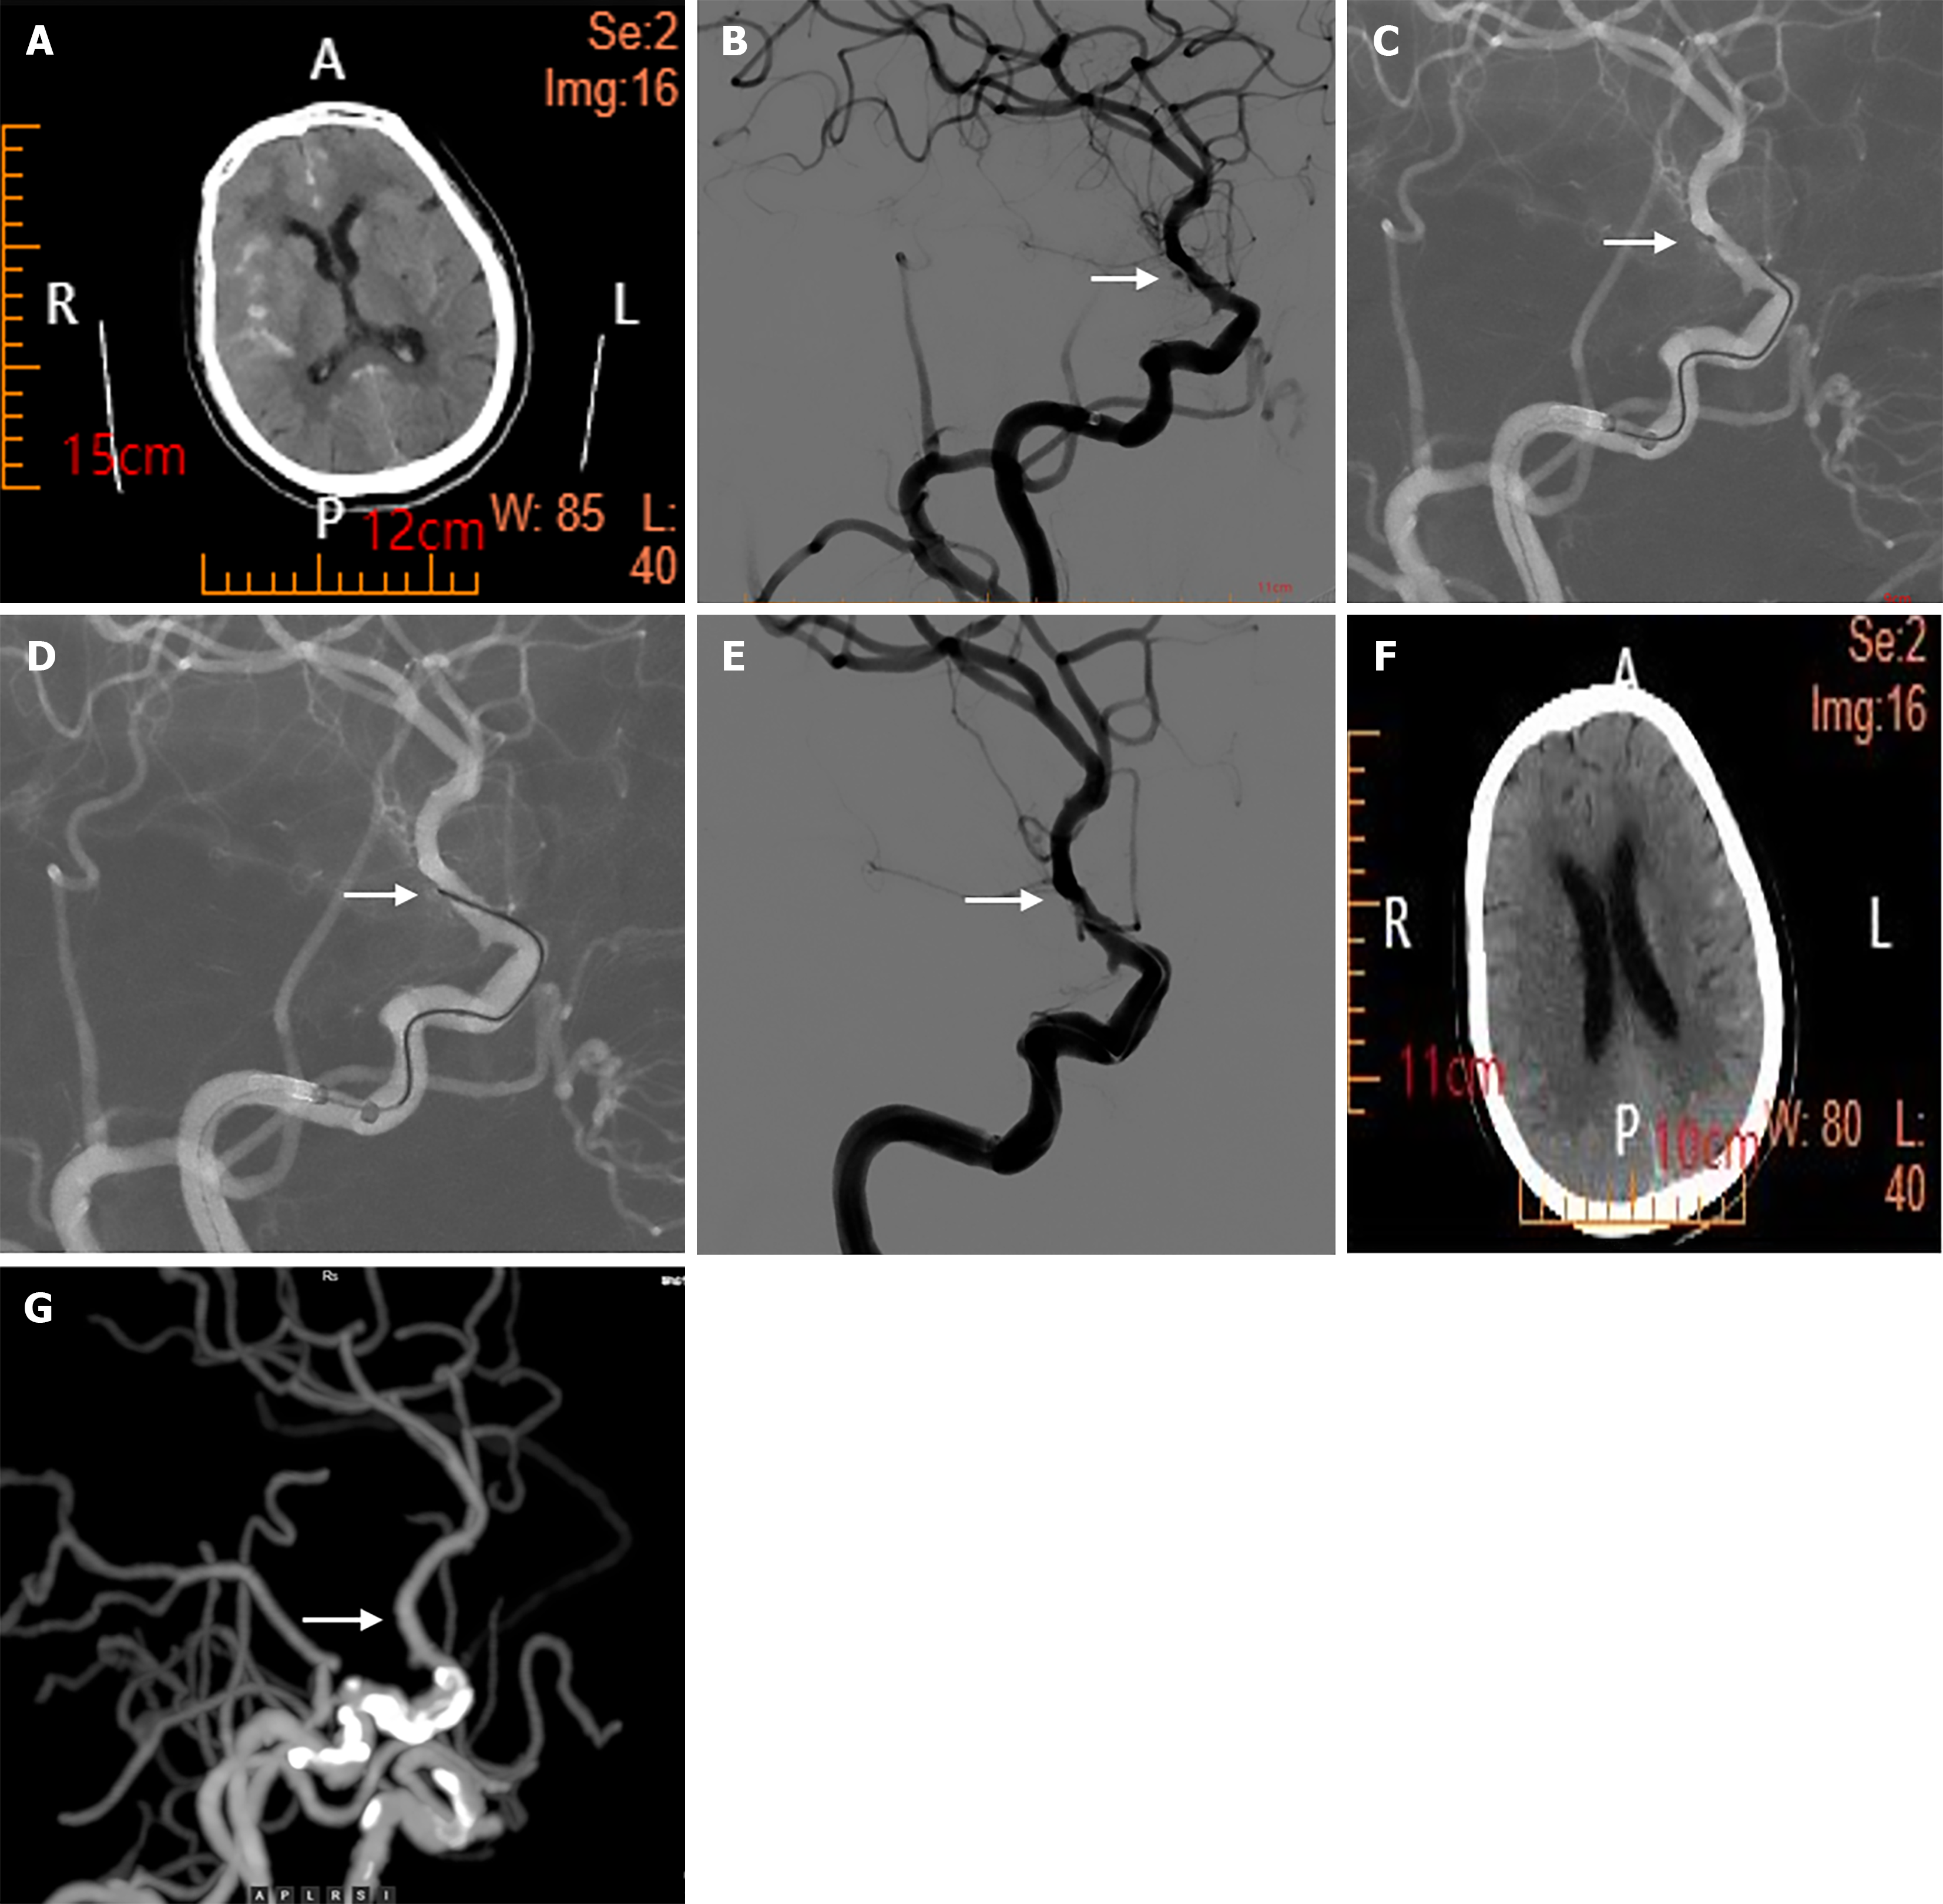

Figure 1 Computed tomography and angiography.

A: Computed tomography(CT) scan showing increased density in the posterior horns of the bilateral ventricles and partial sulci, diagnosed as a subarachnoid hemorrhage; B: Cerebral angiography image showing a saccular bulge in the choroidal segment of the internal carotid artery without contrast agent extravasation, which was speculated to be an arterial ampulla. In addition, a blister-like aneurysm ruptured and bled (arrow); C and D: Show that we used microguidewire electrocoagulation surgery to treat the aneurysm (arrow); E: Shows that after the third continuous electrocoagulation, revisualization of the aneurysm was absent (arrow); F: CT scan reexamination 3 days after surgery shows no obvious subarachnoid hemorrhage; G: CT angiography reexamination 3 months after surgery revealed no contrast agent extravasation in the original lesion, with a good prognosis (arrow).